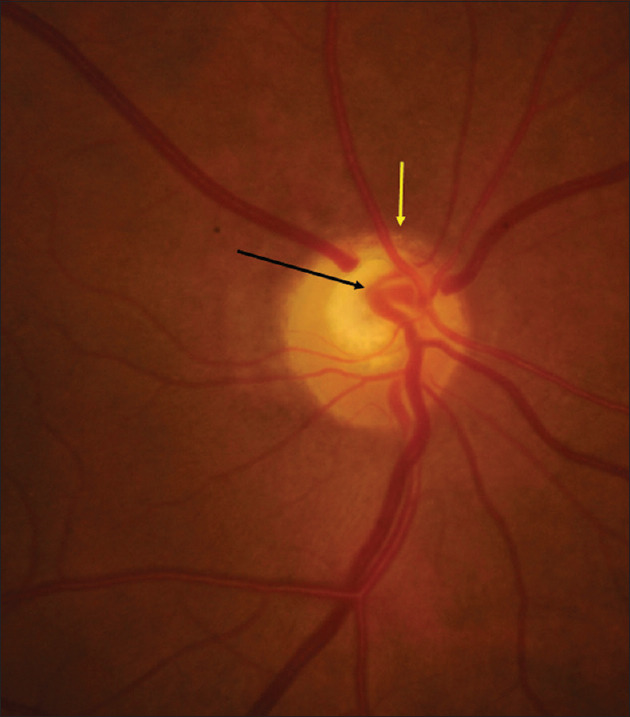

Superior segmental optic nerve hypoplasia misdiagnosed as normal tension glaucoma.

上节段性视神经发育不全误诊为正常张力性青光眼。